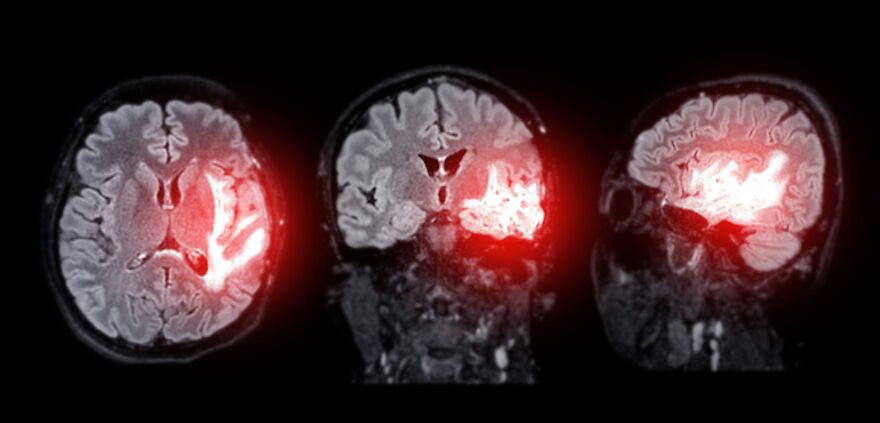

“In rare cases the sudden spike in pressure can rupture blood vessels in the brain leading to subarachnoid hemorrhage,” which is a life-threatening condition where blood seeps between the brain and its protective membranes.